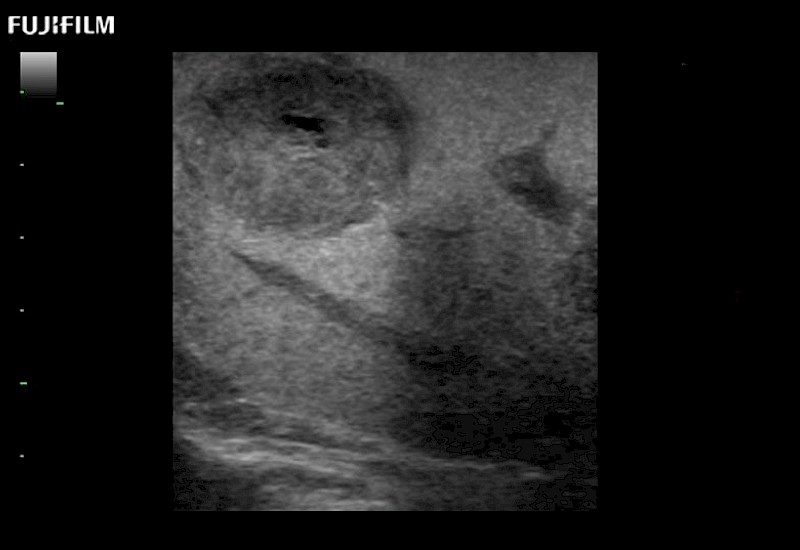

Extraordinary high-resolution digital imaging

- Exceptional near and far-field resolution

- Instant feedback on tumor margin delineation

- Valuable information to guide tumor resections

- Exceptional near and far-field resolution

- Instant feedback on tumor margin delineation

- Exceptional near and far-field resolution

- Exceptional near and far-field resolution

- Instant feedback on tumor margin delineation

- Exceptional near and far-field resolution

- Instant feedback on tumor margin delineation

- Exceptional near and far-field resolution

- Instant feedback on tumor margin delineation

- Exceptional near and far-field resolution

- Instant feedback on tumor margin delineation

- Valuable information to guide tumor resections

- Exceptional near and far-field resolution

- Instant feedback on tumor margin delineation

- Valuable information to guide tumor resections

- Exceptional near and far field resolution

- Instant feedback on tumor margin delineation

- Valuable information to guide tumor resections

- Exceptional near and far-field resolution

- Instant feedback on tumor margin delineation

- Valuable information to guide tumor resections

- Exceptional near and far field resolution

- Instant feedback on tumor margin delineation